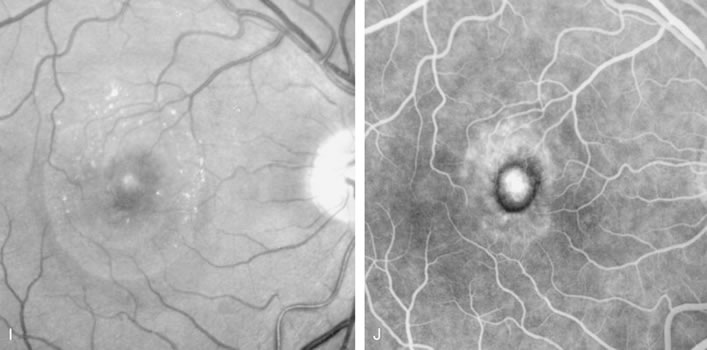

Fig. 20. A. Red-free photograph of a 20-year-old patient with sudden loss of vision to the level of 20/200. There is exudative, neurosensory macular detachment, a few hemorrhages, and lipid exudates. B. Fluorescein angiography reveals the presence of classic choroidal neovascularization (CNV), which appears to be juxtafoveal (<200 μ from fixation). Given the size of the CNV and its proximity to the fovea, it was decided to treat the patient with photodynamic treatment (PDT). C. Red-free photograph of the same eye 2 weeks after PDT; there is increased subretinal exudation D. Fluorescein angiography demonstrates that the CNV is still actively leaking. E. Red-free photograph 4 weeks after PDT demonstrates further increase in the size of the neurosensory macular detachment, subretinal hemorrhages, and lipid exudation. F. Fluorescin angiography reveals that the CNV has extended under the fovea. Given the young age of the patient, an inflammatory component of the neovascular process was suspected. It was decided to give a posterior, subtenon injection of triamcinolone acetonide, 40 mg/1 mL. G. Two weeks after steroid treatment there is partial reabsorption of the subretinal fluid. H. Fluorescein angiography demonstrates contraction of the CNV. I. Four weeks after injection of triamcinolone there is further reduction in the degree of neurosensory detachment; vision had improved to 20/60. J. Fluorescein angiography demonstrates that the CNV is smaller and less active (less leakage).

FA is needed to assess response to laser photocoagulation of a CNV and to diagnose recurrent membranes.51,54 The authors generally obtain angiograms 2 weeks, 1 month, 3 months, and 6 months after treatment. The risk of recurrence is greatest during the first 3 months, and the patient, who often has decreased vision due to prior neurosensory detachment, may be asymptomatic. FA is also needed to evaluate the results of PDT. In the original protocol of the Verteporfin in Photodynamic Therapy (VIP) and Treatment of Age-Related Macular Degeneration with Photodynamic Therapy (TAP) studies, a fluorescein angiogram was obtained every 3 months, and if there was persistent leakage from the CNV PDT was applied again (see Fig. 1820).60